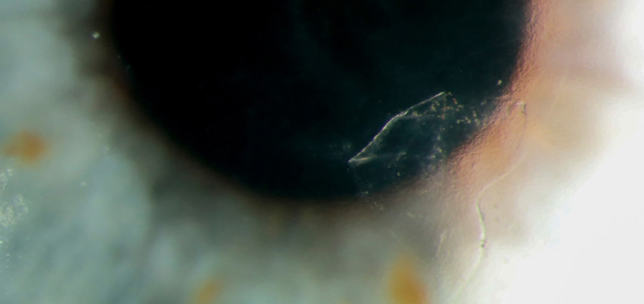

The ANTerior Segment Imaging Competition from Eye News and Keeler promotes and celebrates the work of slit-lamp imaging, culminating in cash prizes and exposure for its winners.

After a successful run in 2024, the ANTS Imaging Competition returned this year with another overwhelming response and our judges were thrilled to have so many amazing images to choose from. We would like to offer a huge congratulations to our winners, honorary mentions, and shortlisted entries, all of which can be seen below. So, without further ado, here some of the best ophthalmic imagers, optometrists and allied professionals in the UK right now: